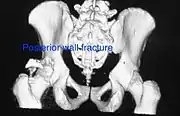

- Posterior wall fracture

Posterior wall fracture as seen on 3-D CT scan

Posterior column and wall fracture as seen on 3D CT

Both column fracture showing floating weight bearing dome